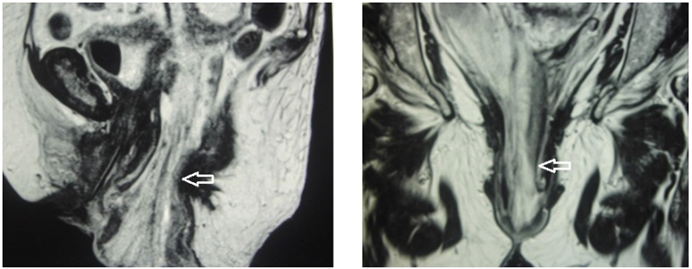

Con lo anterior, se planteó el diagnóstico de evisceración intestinal transvaginal incarcerada con perforación y obstrucción intestinal en resolución. Se inició nutrición parenteral total cinco días después y se solicitó una resonancia magnética abdominopélvica que reveló introito vaginal ampliado de 5 cm de diámetro anteroposterior, el cual estaba ocupado en su interior por asas intestinales y mesenterio protruido (Figura 3).

La paciente fue programada para cirugía electiva una vez que se confirmó la mejoría de los indicadores nutricionales. En la intervención quirúrgica se encontró prolapso de la cúpula vaginal con un orificio central por donde protruía intestino delgado (íleon), perforado y con la mucosa evertida en su totalidad. Con el diagnóstico de evisceración intestinal transvaginal incarcerada con perforación intestinal, se realizó sacrocolpopexia con malla reticular de polipropileno en Y invertida, plastia de Douglas, resección y anastomosis intestinal termino-terminal. El abordaje inicial fue por vía vaginal, se liberó el asa intestinal incarcerada y perforada, luego por laparotomía se realizó la resección y anastomosis del íleon y sacrocolpopexia con malla de polipropilene y peritonización de lecho pélvico (Figura 4).